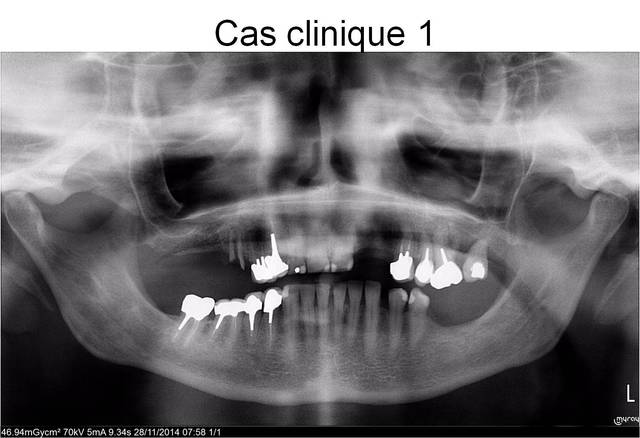

je n'ai ni le nombre de cas ni la prétention de détenir la vérité, mais une image vaut amha bien des discours...

si tu regardes attentivement ce qui c'est passé au niveau gingival en seulement 24 heures, je pense que tu peux aisément en tirer des conclusions entre MCI et mise en charge à 48h...non?

perso, je suis intimement persuadé que çà change tout, du moins au niveau des résultats esthétiques des tissus périimplantaires...

peut être que posit pourrait compiler des cas avec photos comme je l'ai fait type post op/1 semaine/15j, etc...pour étudier (au moins au niveau photographique) la réponse tissulaire gingivale...

cas clinique MCI post-extraction